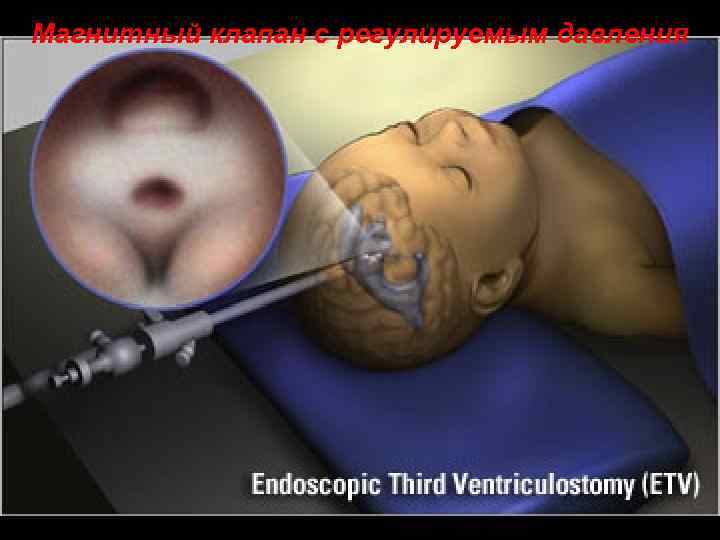

Магнитный клапан с регулируемым давления 103